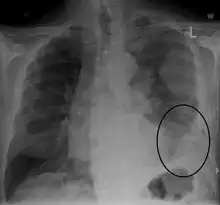

![]() | |

CT scan showing a left sided mesothelioma with an enlarged mediastinal lymph node | |